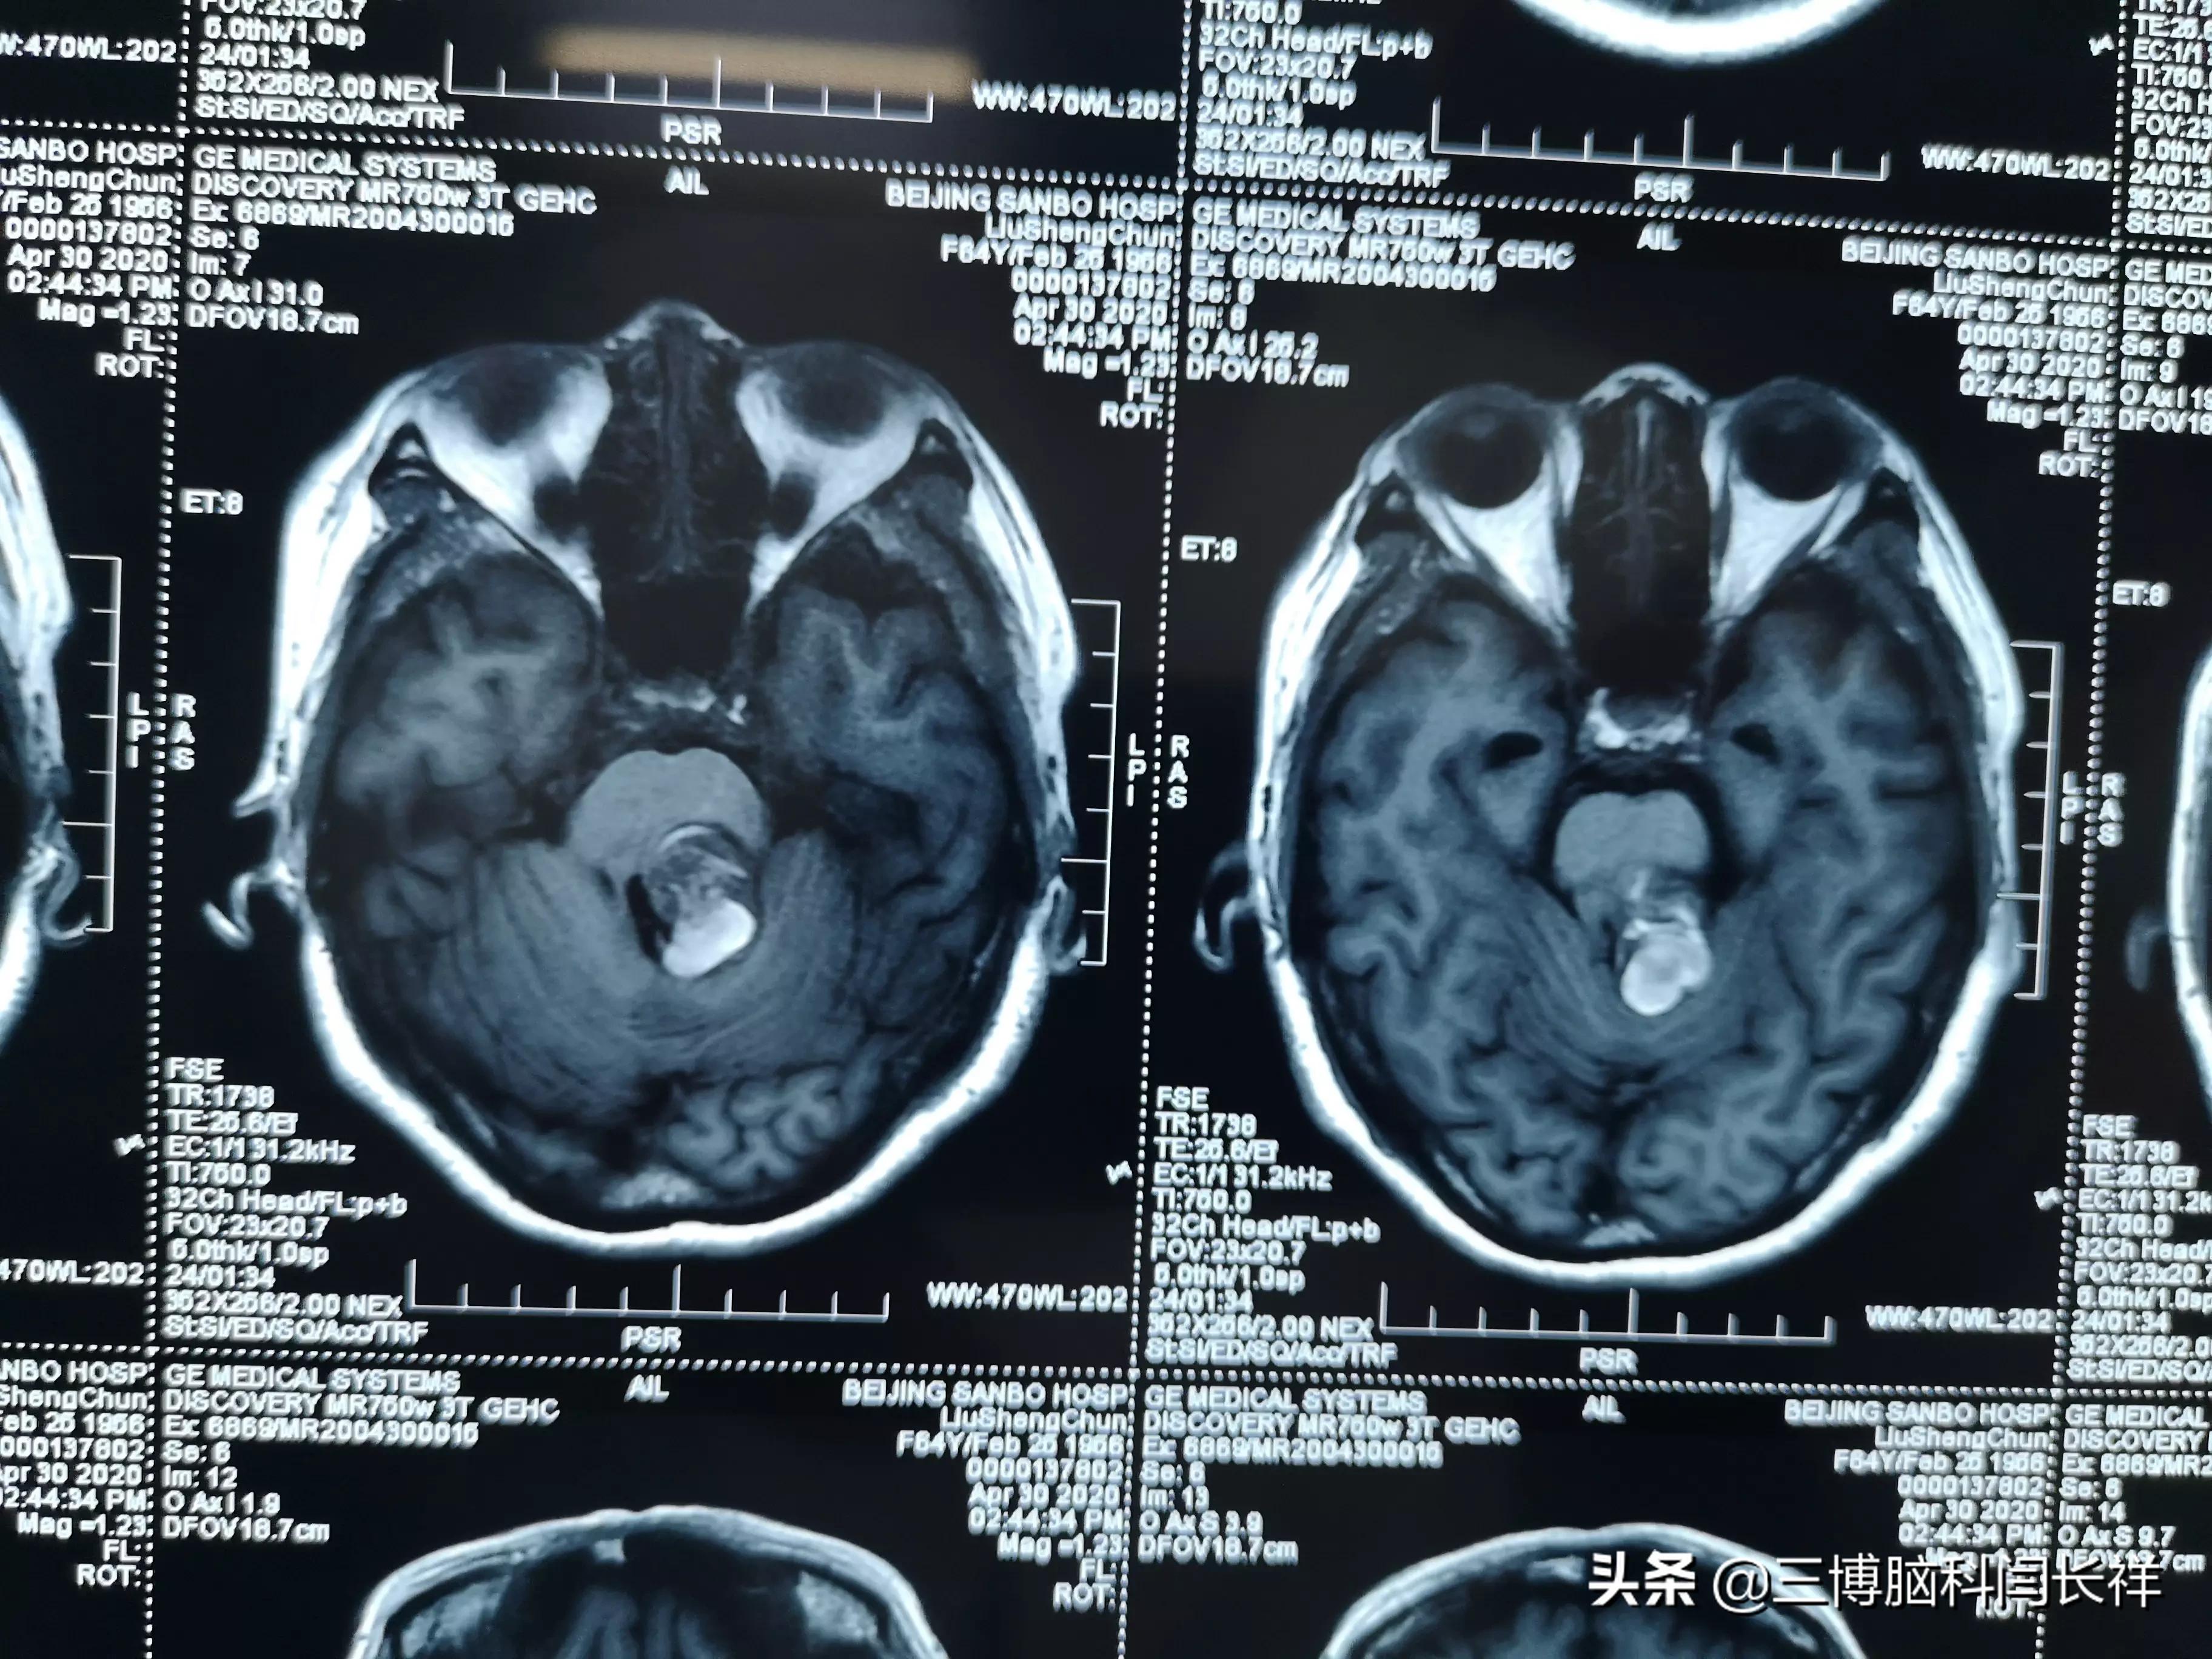

脑干海绵状血管瘤——之手术治疗(省中神外病例分享 第13期)

脑干海绵状血管瘤需及时治疗